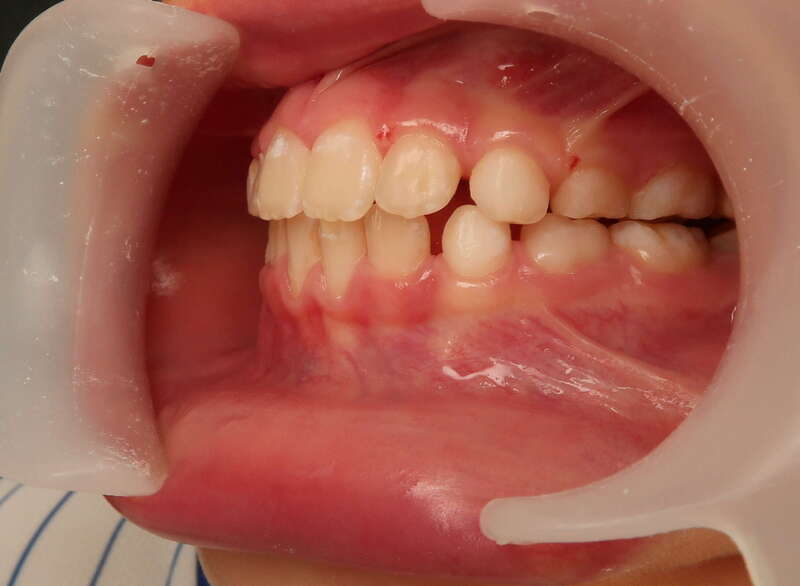

Cas n°1 traité par aligneurs - adolescent

Ce cas d’une adolescente illustre la correction d'une Classe II avec supraclusion par aligneurs. La stratégie thérapeutique a reposé sur une distalisation séquentielle de l'arcade supérieure. Ce mouvement précis a permis de reculer les dents maxillaires étape par étape pour annuler le surplomb (overjet) sans extractions.

• Correction fonctionnelle : Retour à un engrènement de Classe I stable et correction du recouvrement vertical.

• Esthétique restaurée : Harmonisation globale du sourire et du profil.

• Approche moderne : Un traitement discret, confortable et hautement prévisible.

Le résultat final montre une occlusion saine et un sourire parfaitement aligné, garantissant une santé dentaire et articulaire optimale pour l'avenir.